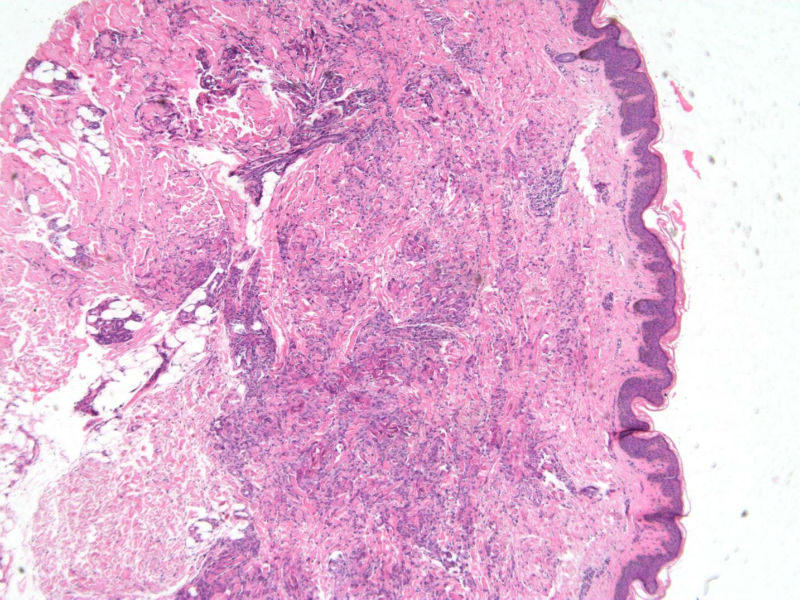

患者 男,8岁,双小腿渐粗红肿伴痒20余天,皮疹渐扩大,且出现硬化萎缩,入院后发现肺吸虫(+)。临床考虑:肺吸虫病硬皮病。请问斑竹大人考虑啥?

• 双小腿红肿伴痒20余天图1

图1

肺吸虫引起的嗜酸性粒细胞增多性疾病

肉芽肿性病变。肺吸虫能继发硬皮病吗?

肉芽肿中央不是凝固性坏死,好像是胶原纤维,否为环状肉芽肿或类脂质渐进性坏死

要考虑Wells综合征,依据有肺吸虫检查阳性、皮疹表现为肉芽肿样表现,可见到火焰征,不知道临床上血液分析检查结果如何,以及其他的检查结果怎么样?

肺吸虫皮下结节表现为肉芽肿炎症,这里的图片所显示的就是真皮及皮下组织的肉芽肿炎症,若是肺吸虫所致,按理是多少能见到嗜酸粒细胞的,但这里确实是没有看到,也没见可以的虫体征象,是没切到?也似乎没见很明显的硬皮病相关表现。

但是结合病史,患儿的皮肤改变可能还是用跟肺吸虫有关的东西来解释为妥?

补充(临床医生邮件提供)该病人是一个8岁的小男孩,此次就诊主因双小腿肿胀发硬伴痒20天入院。既往体健,无内脏疾病史,入院时无发热、咳嗽、咳痰,无腹痛、腹泻等不适。专科检查:双小腿弥漫肿胀性褐色斑块,皮疹边界清楚,左小腿较右小腿肿胀明显,左小腿皮肤弹性较正常差,皮温正常,皮肤表面未见抓痕,未见红斑、丘疹、结节等,未见糜烂、破溃。入院查血分析嗜酸性粒细胞百分之六十多,余未见明显异常;体液免疫是IgE升高明显,有一百多倍吧,具体记不清。行肺吸虫皮试阳性,胸部CT及全腹CT检查均可见感染性病变,颅脑CT未见异常。给予杀虫治疗1疗程后,左小腿肿胀明显消退,现两小腿粗细相当,左小腿肿胀发硬也明显缓解,但褐色色沉一直未见明显消退,而且还向大腿蔓延,未见明显肿胀发硬的改变。患者现无瘙痒、肿胀感等不适。患者皮疹并不是肺吸虫病的典型皮疹,故行病理检查明确皮疹是否于肺吸虫病相关。

1、患者的皮损与血液中嗜酸性粒细胞增多有关,病理改变的确类似Wells综合征的灶状坏死,但没有特异性。

2、嗜酸性粒细胞增多可以表现为毛囊炎,蜂窝织炎,脂膜炎,筋膜炎,嗜酸性皮病和增多综合征等,

3、其产生的原因常常是寄生虫,此例明确有肺吸虫。所以两者有明确的相关性。